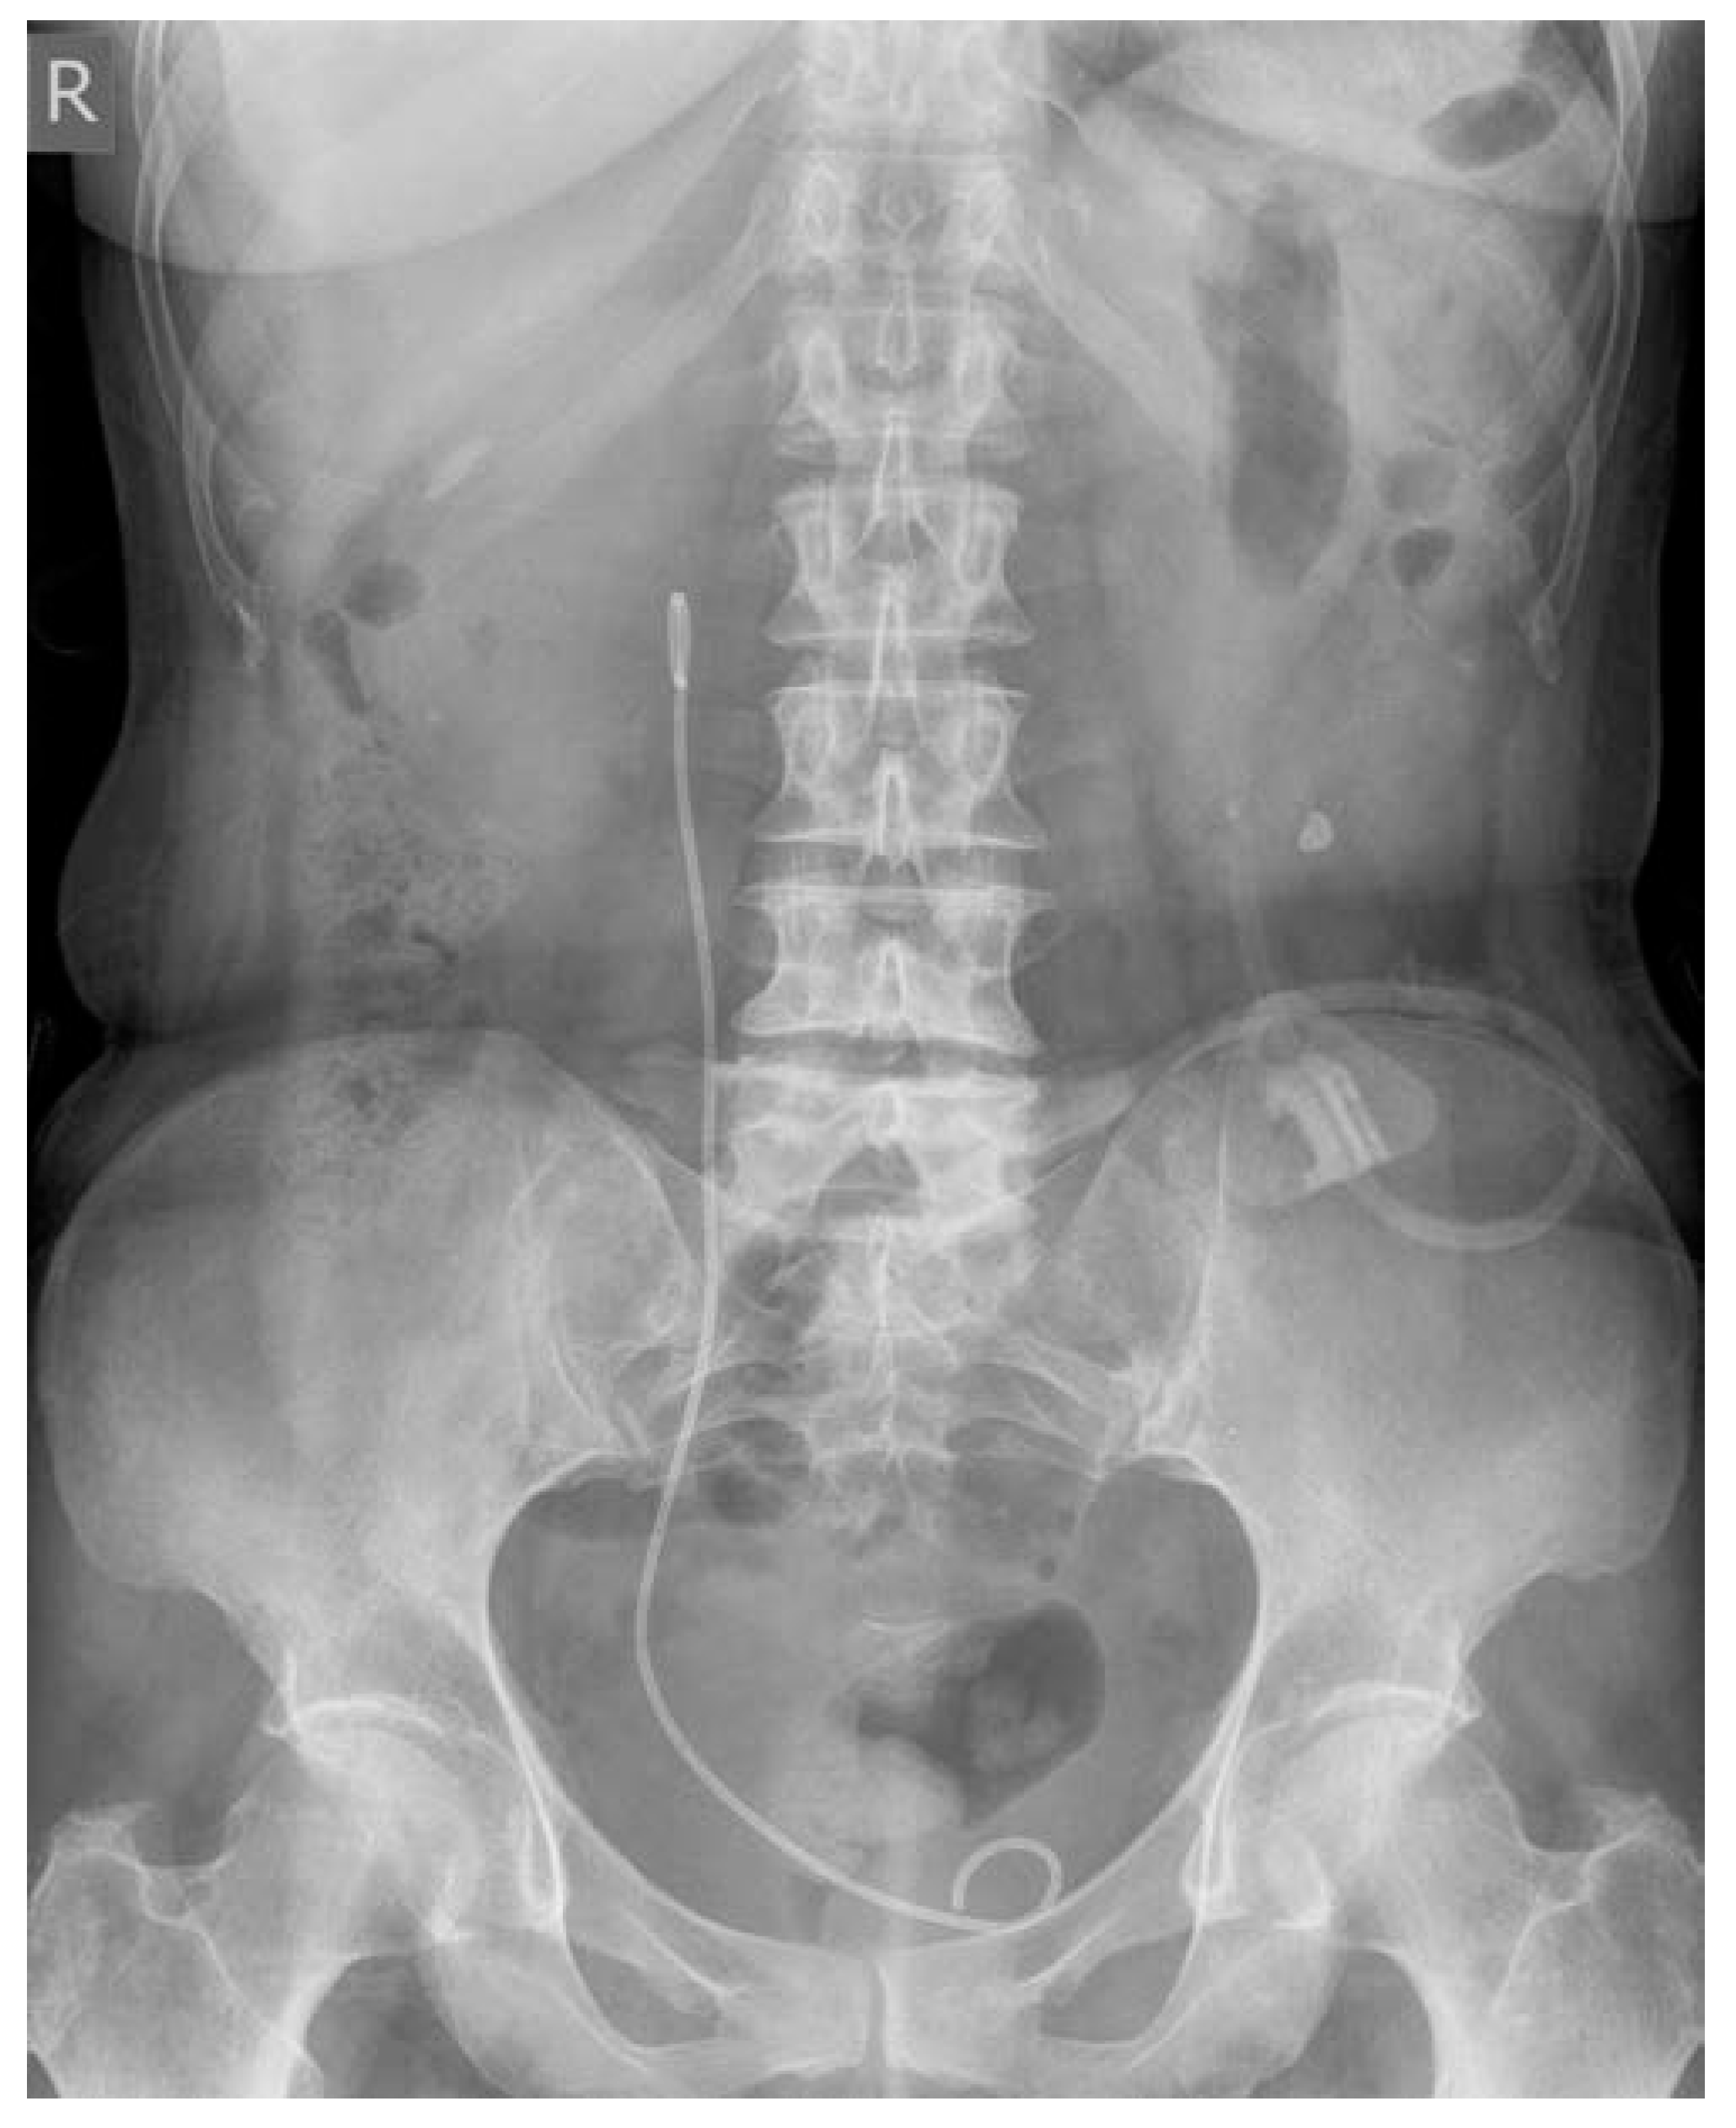

2. Case Report